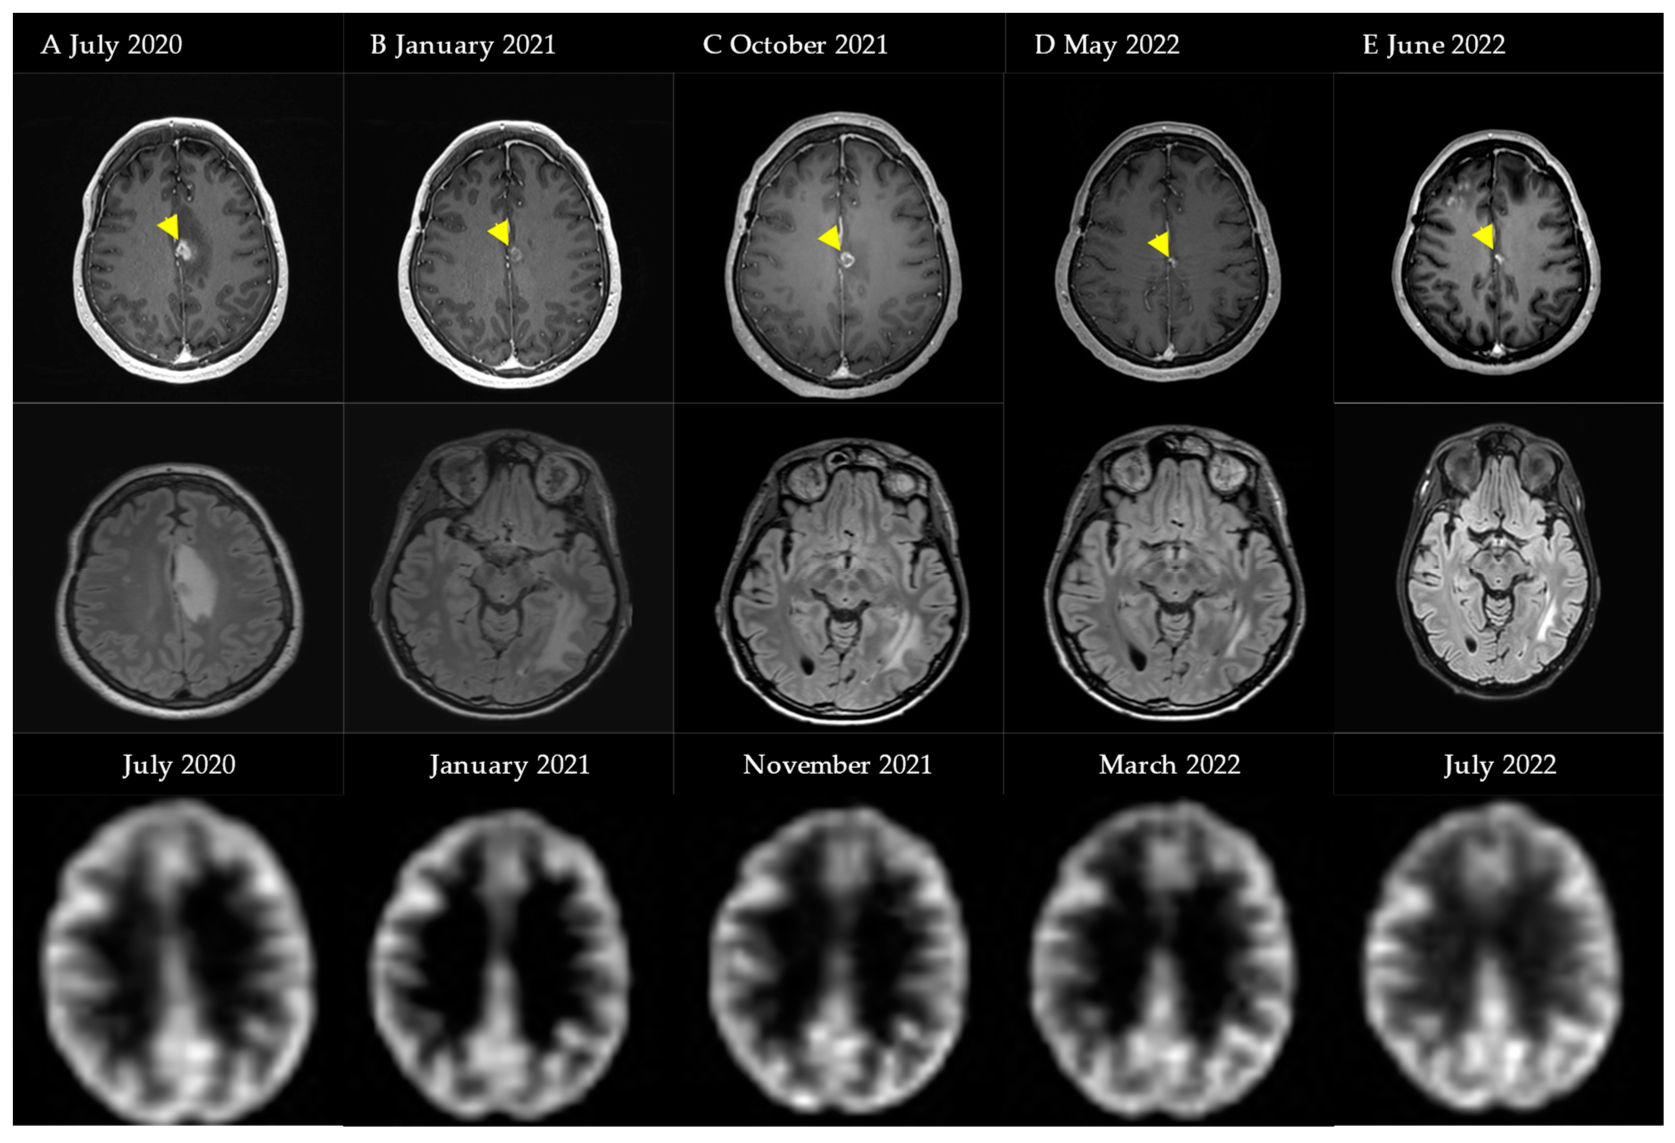

4.2. Case Illustration 2